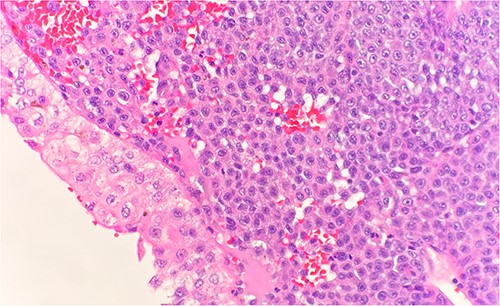

Microscopic examination shows extensive involvement of the bladder wall by sheets of small round blue tumor cells showing cleaved and irregular nuclear contours and conspicuous nucleoli. Mitotic activity is frequent and majority of cells show scant amphophilic cytoplasm with few foci showing more abundant bubbly cytoplasm and others with clear foamy cytoplasm (Fig. 1). A rare foci of finely granular brown pigment representing melanin and moderate cytological atypia in a small area of surface urothelium. Similar morphological features are seen in colonic biopsy specimens (Fig. 2).

Microscopic examination reveals sheets of round cell between unremarkable colonic crypts. H&E stain 40×.